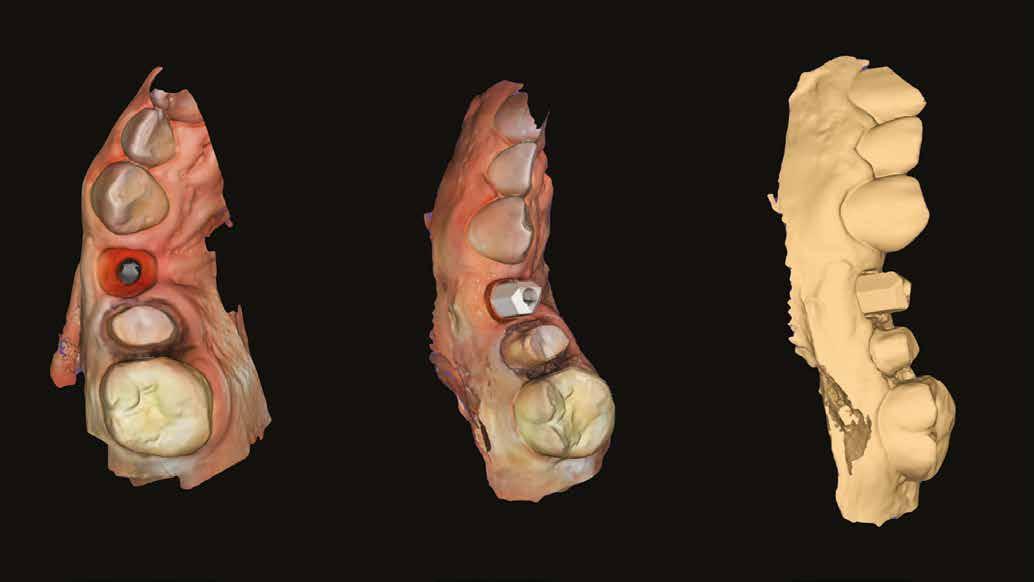

Az 50 éves nőpáciens az alsó és felső állcsont területén egyaránt panaszt (fájdalom, ráharapási érzékenység) okozó, harmadfokban mozgatható fogak miatt jelentkezett rendelőnkben. Az általános anamnézisben említést érdemlő betegség, műtét nem szerepelt. Az elvégzett klinikai és radiológiai vizsgálatok (1–2. ábra) alapján fogai reménytelen parodontális státusúnak bizonyultak, hosszú távon sem megtartásuk, sem protetikai célú felhasználásuk nem volt lehetséges. A parodontális prognózis a fogak eltávolításának abszolút indikációját jelentette. Ezáltal mindkét állcsontban teljes foghiány kialakulásával kellett számolnunk. A protetikai szemléletű, „visszafelé” tervezés elveit követtük a hosszú távú funkcionális, esztétikai siker és szöveti stabilitás elérése érdekében: mindkét állcsontban overdenture típusú fogpótlás készítése mellett döntöttünk. A megfelelő implant-protetikai rehabilitáció alapja az implantátumok megfelelő pozicionálása. A korábbi parodontális kórfolyamat következtében a processus alveolarisokat érintő eredendő csontdeficittel kellett számolnunk, amelyet tovább súlyosbíthatott volna a hagyományos extrakciós technikát követő involúciós atrófia. Ezért a páciens kivizsgálása és megfelelő előkészítése után a fog eltávolításával egy időben PRF

A gyógyulási időszakot követően a csontos gyógyulás ellenőrzése és az implantáció tervezése céljából állcsonti CT-felvételt készítettünk. A CT-felvételen tökéletes csontos gyógyulást észleltünk, az alveoláris csont volumene

Fergeteges

teljes mértékben megtartott, a vertikális augmentáció a tervezettnek megfelelő eredményű volt (13–15. ábra), a klinikai kép is ennek megfelelően alakult, optimális menynyiségű keratinizált ínnyel és azt adekvát sebészi technika eredményeképpen megtartott vesztibulummal (16–17. ábra). Az alsó és felső állcsontba 4-4 darab Bredent COPA Sky implantátumot ültettük, D1-D2 csontminőség mellett,

35 Ncm primer stabilitást mértünk. Nyílt gyógyulási protokollt alkalmazva az ínyformázókat is behelyeztük, amelyek körül az ínyt csomós öltésekkel zártuk (18–20. ábra) Amennyiben lehetséges, mindig nyílt gyógyulási protokollt választunk, így biztosítva elegendő időt a lágyrészek maturációjához (29). Kiemelendő, hogy az irodalmi adatoknak (30, 31, 32) és saját tapasztalatunknak megfelelően az íny biotípusának jelentős, pozitív irányú változását észleltük. Az implantátumokra 180 nap gyógyulási időszakot követően (minden implantátum stabilitása Periotesttel –8-as értékű volt) hagyományos lenyomatvételi módszer és egyéni értékű artikulátor használatával a fogtechnikus (D1 Dental Kft., Garamvári Csaba) overdenture típusú fogpótlást készített (21. ábra)

A protetikai rehabilitációt követően 9 hónappal az alveoláris struktúrák stabilak, a röntgenfelvételen a csontállomány megtartott, a beteg panaszmentes, rágó funkciója kifogástalan, az esztétikai eredménnyel teljes mértékben elégedett (22–23. ábra)